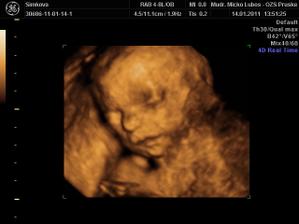

Naša princezná (v brušku...)

Stráááášne sa na ňu tešíme.......

je to mala herecka....ukazala nam vsetko....moc sa na nu uz tesime